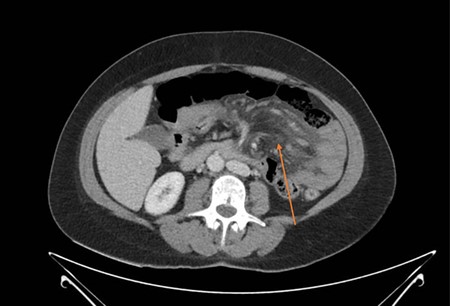

Blood tests revealed a mild leucocytosis of 13.7 × 10^9 g/L (4.0–11.0 × 10^9 g/L) and an elevated lactate of 3.1 mmol/L (0.5–2.0 mmol/L). The remaining laboratory tests were otherwise unremarkable. Her plain abdominal film demonstrated small-bowel dilatation in the upper abdomen, suggestive of a developing bowel obstruction. She proceeded to a computed topography (CT) scan of the abdomen and pelvis that demonstrated a number of findings; these included prominent oedema throughout the small-bowel mesentery associated with enlarged mesenteric lymph nodes, free fluid in the rectovaginal pouch and right iliac fossa, and wall thickening involving most of the jejunum (Fig. 1). The thickened bowel loops and mesenteric oedema were located on the left side of the abdomen, consistent with the patient’s symptoms, and were associated with the impression of a mesenteric swirl, leading to concerns regarding possible internal herniation.

CT demonstrating jejunal wall thickening and mesenteric oedema (arrow).